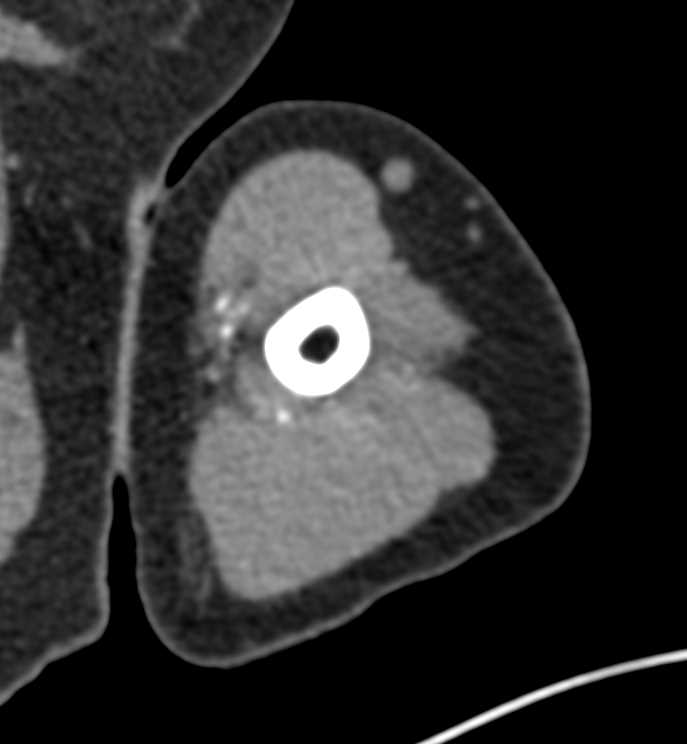

Brachial Artery Occlusion